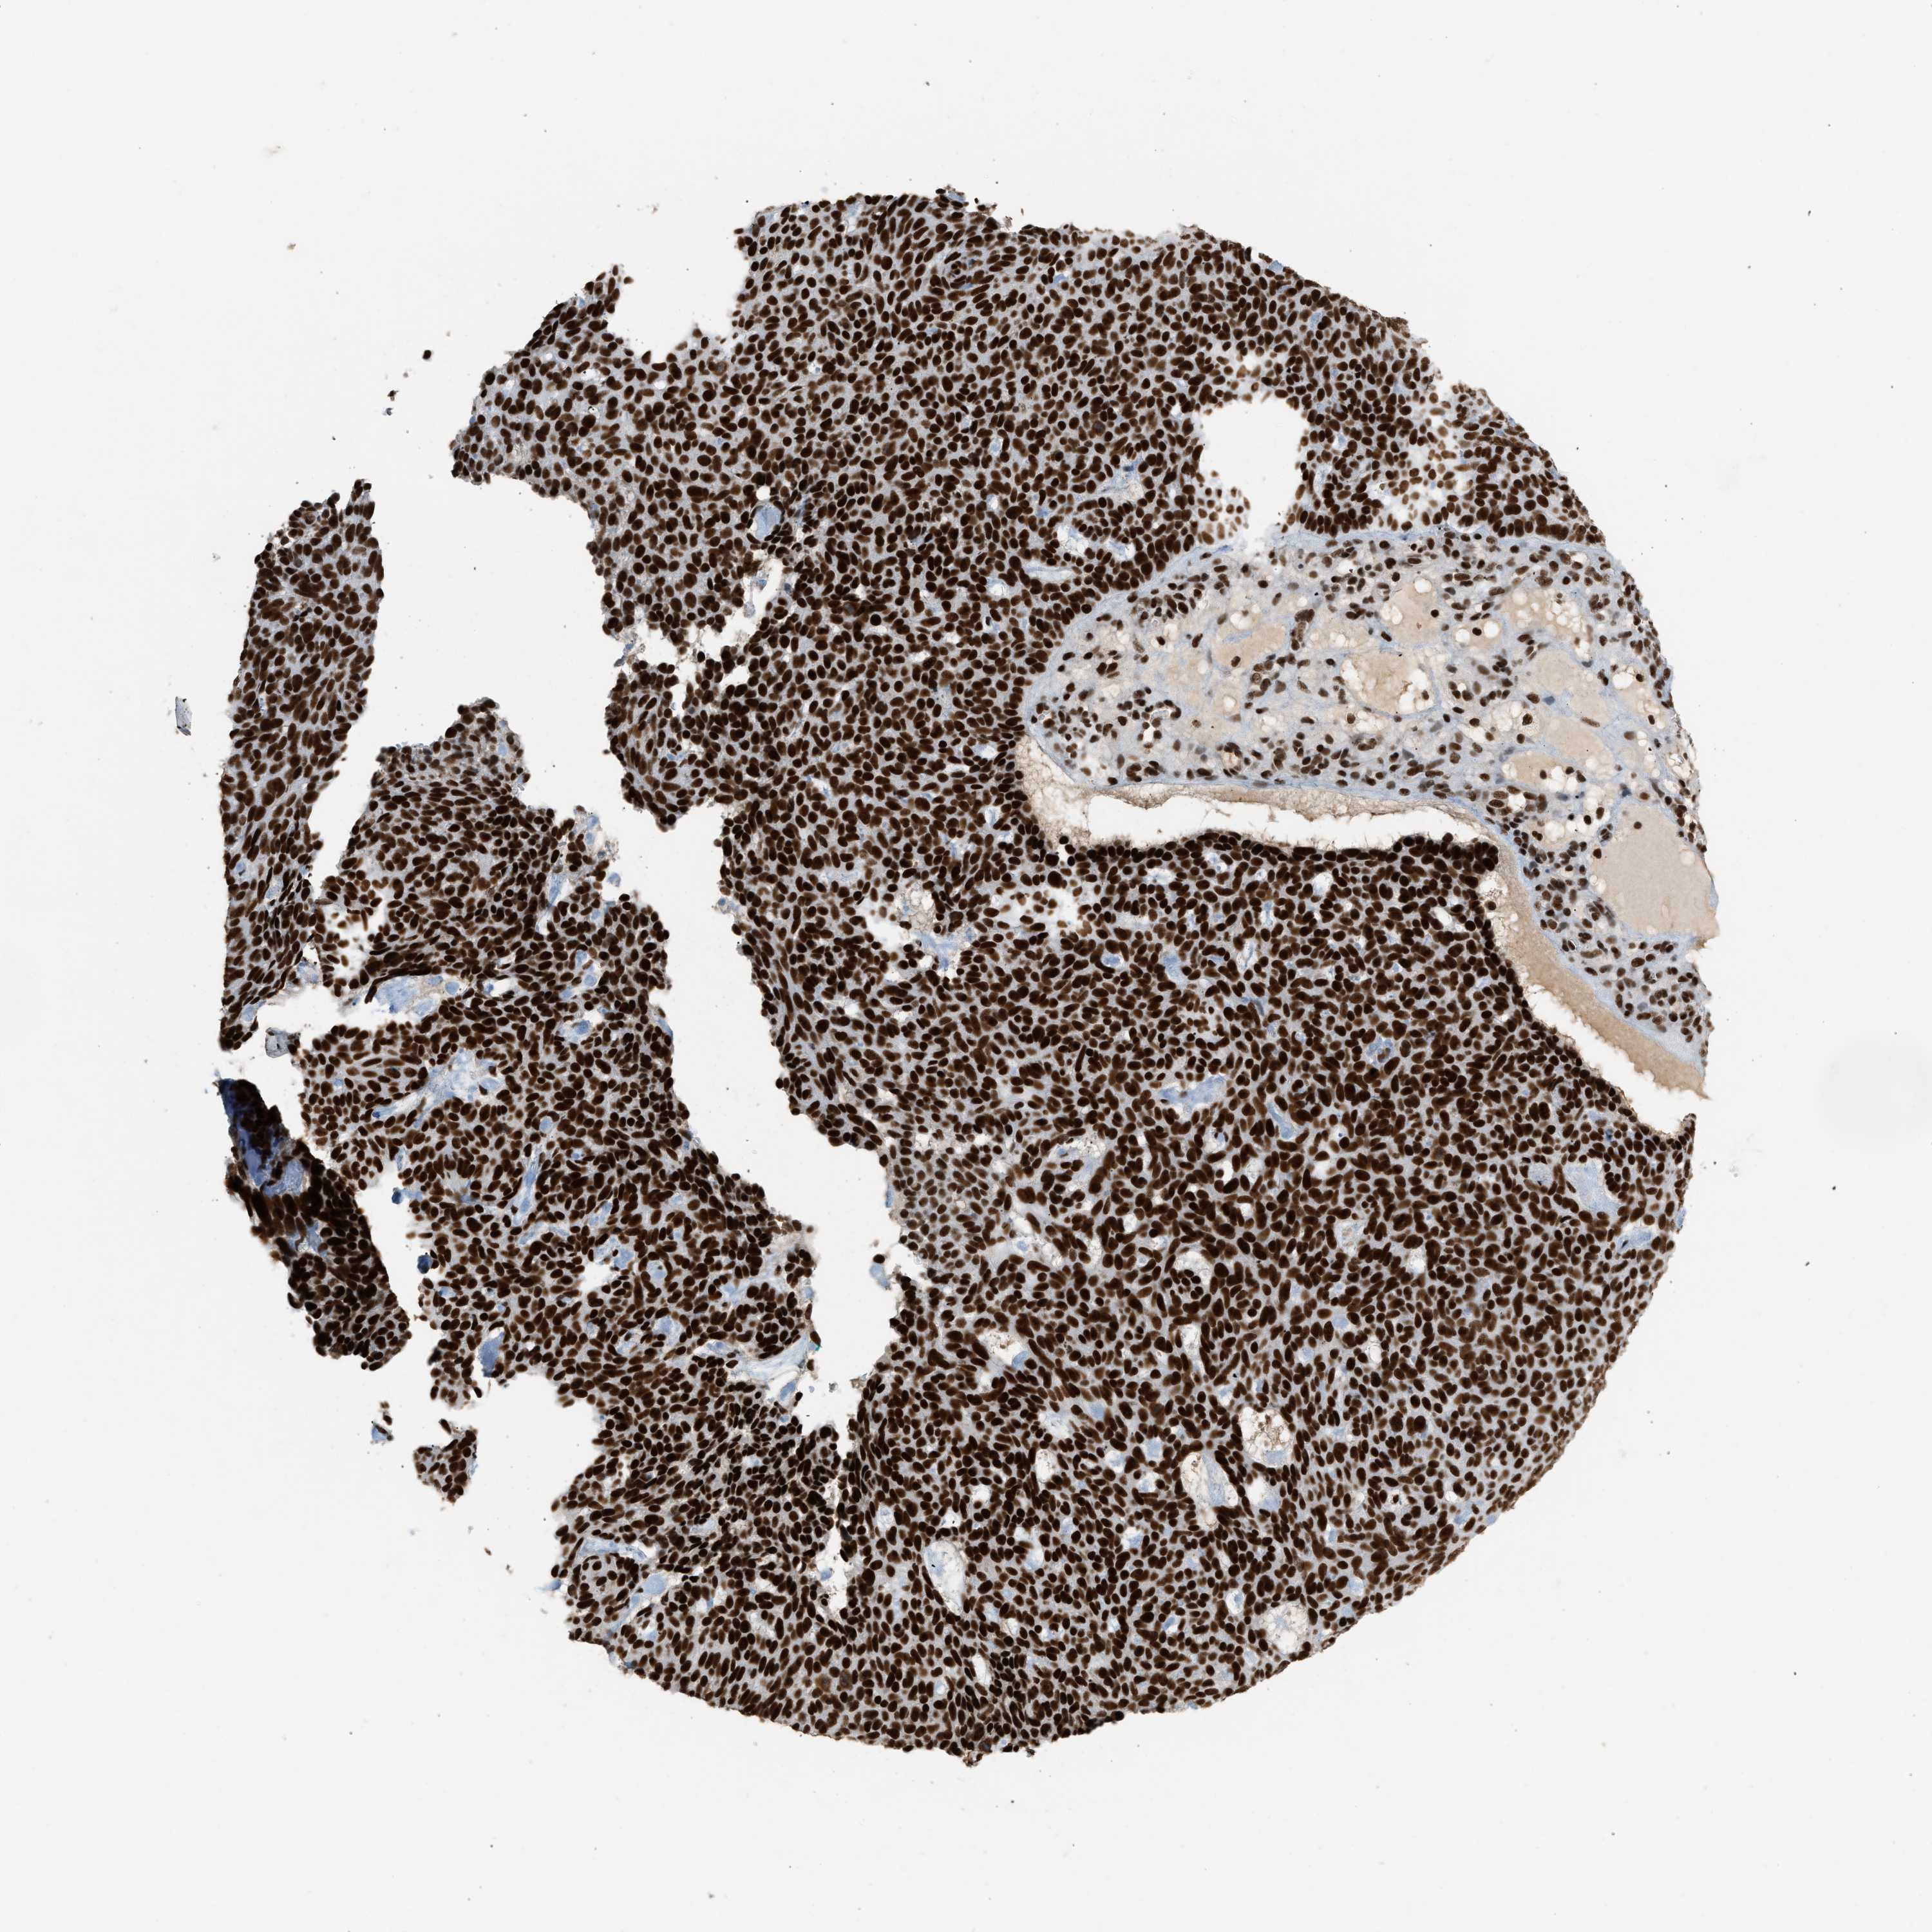

SKIN CANCER - Protein expressioni

A mouse-over function shows sample information and annotation data. Click on an image to view it in a full screen mode. Samples can be filtered based on level of antibody staining by selecting one or several of the following categories: high, medium, low and not detected. The assay and annotation is described here.

Antibody stainingi

Antibody staining in the annotated cell types in the current human tissue is reported as not detected, low, medium, or high, based on conventional immunohistochemistry profiling in selected tissues. This score is based on the combination of the staining intensity and fraction of stained cells.

Each image is clickable and will lead to virtual microscopy that enables deeper exploration of all samples and also displays staining intensity scores, fraction scores and subcellular localization as well as patient and tissue information for each sample.

Antibody HPA018248

Antibody HPA019127

Antibody CAB009196

Staining

High

Medium

Low

Not detected

Intensity

Strong

Moderate

Weak

Negative

Quantity

>75%

75%-25%

<25%

None

Location

Nuclear

Cytoplasmic/membranous

Cytoplasmic/membranous,nuclear

Squamous cell carcinoma in situ, NOS

Squamous cell carcinoma, NOS

Squamous cell carcinoma, metastatic, NOS

Basal cell carcinoma